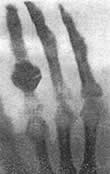

伦琴断定这是一种新射线,一种从未曾记载过的东西。伦琴用它拍出了一张肉淡骨浓的手掌照片,有人用它鉴别古画,一时引起轰动,伦琴将这具有非凡魅力的射线命名为“X”射线。